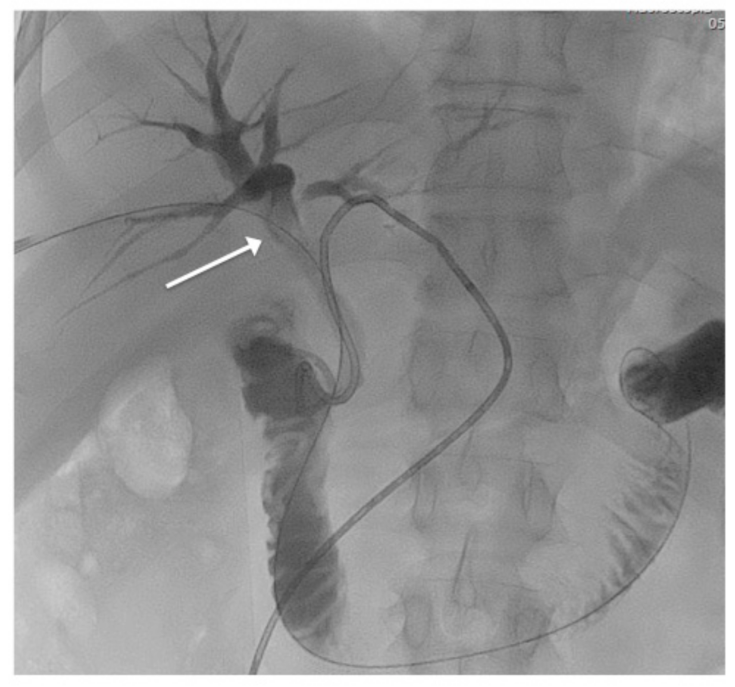

2.1. Patient 1

2.3. Technique and Procedure

3. Results